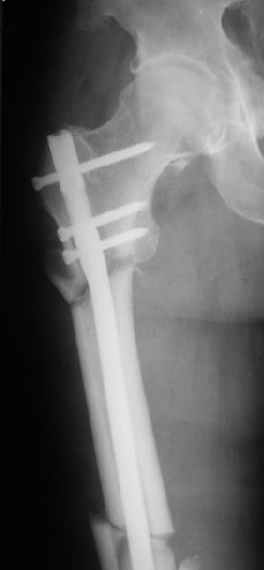

Могу скромно напомнить о существовании стержня нашей модификации.

В частности, на проксимальном конце сделано еще одно дополнительное статическое отверстие. Можно ввести в проксимальном отделе 4 винта, из них 3 статические (2 в круглые отверстия и 1 по нижнему краю овального). Картинки в приложении. На дистальном конце стержня тоже кое-что улучшено. Спрашивайте в аптеках, как говорится. Выпускается предприятием "ЦИТО" (Москва), то есть это малобюджетное решение.